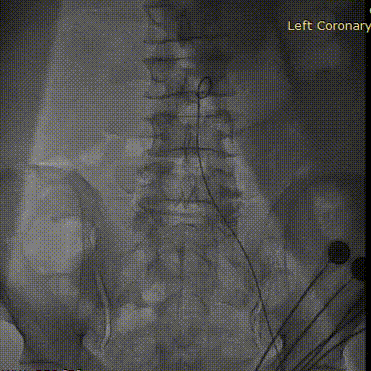

降主动脉再次造影

复查经胸超声提示瓣膜工作良好,心功能即刻有明显改善,左室射血分数由术前的20%提高到29%,从患者进入导管室到瓣膜释放,仅用时50分钟。完成手术入路缝合后,患者返回心脏瓣膜病介入中心重症监护病房,术后第二天即拔除临时起搏电极,解除压迫绷带。患者自觉憋气症状明显好转,感叹终于可以平卧躺下,并开始下地活动。复查肌酐85umol/l,肾功能也在术后明显改善,血压稳定在100/60mmHg左右。